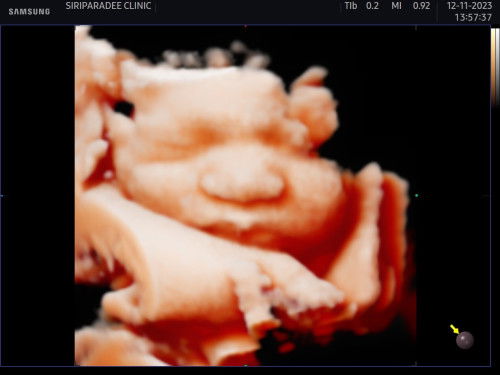

ย้ายวันกันบ้างรึยังคะ บ้านนี้หมอให้เลือกวันผ่าได้เลย น้องหนัก 2,5++ กรัม 35 วีคค่ะ ไตรสมาสสามบำรุงนมหมีจืดสีเหลือง+กล้วย+ผลไม้ มื้อเช้า+บ่ายกินปกติ ตอนนี้มีอาการเจ็บเตือนบ้าง เพราะหัวน้องจ่ออยู่ข้างล่างแล้วค่ะจี๊ดมากเวลาดิ้นแรงๆ นอนไม่ค่อยหลับ ท่าที่นอนสบายที่สุดบ้านนี้คือนอนหงาย😂 #ขอคำแนะนำหน่อยค่ะ #คุณแม่ๆช่วยแนะนำหน่อยค่ะ #ท้องแรกคะ

วันนี้33.5 วีคค่ะ มีอาการจี๊ดๆเวลานอนตรงท้องน้อยแต่นานๆทีถึงเป็นไม่บ่อย แต่ปวดอึแต่ไม่อึค่ะแค่เหมือนปวดอึ น้องดิ้นดีแต่เหมือนจะเริ่มถีบๆที่ใต้ราวนมกับฝั่งท้องซ้ายขวาบ้าง แบบนี้เรียกเจ็บเตือนกับลูกกลับหัวแล้วรึเปล่าคะ #ขอคำแนะนำหน่อยค่ะ #ขอบคุณสำหรับคำตอบค่ะ #คุณแม่ๆช่วยแนะนำหน่อยค่ะ #ท้องแรก #ธีมธันวา66 #ลูกชาย